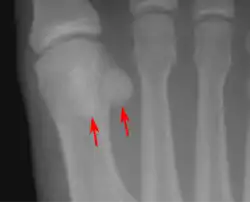

استخوان کُنجدی یا استخوان سزاموئید (انگلیسی: Sesamoid bone) به استخوانهای کوچک و گردی گفته میشود که در لابهلای زردپی یا ماهیچه قرار گرفته و با زردپی، کپسول مفصلی یا ماهیچه احاطه شدهاند.

| TA2 | 374 |

استخوانهای کنجدی اصولاً در دست و پا وجود دارند (مانند استخوان کشکک و استخوان نخودی) و در مسیر زردپیها (تاندونها) قرار گرفته و کارایی آنها را بیشتر میکنند. تعداد استخوانهای کنجدی در دست افراد مختلف متفاوت است. استخوانهای کنجدی باعث افزایش مزیت مکانیکی و محافظت از اتصالات ماهیچه و زردپی میشوند.

استخوانهای کنجدی تحمل فشار و تنش زیادی را در شرایط عادی بعهده دارند. تنش بیش از اندازه میتواند زردپیهای پیرامون این استخوانها را، اغلب بدون هیچ دلیل روشن، ملتهب نماید، اما صدمات کنجدیها در فعالیتهایی مانند رقص باله، جهش و پرش، دویدن، و ورزشهای هوازی سنگین شایع است.